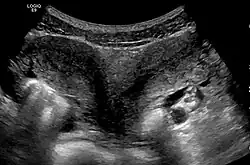

Die Diagnose wird in der Regel durch Sonografie gestellt.